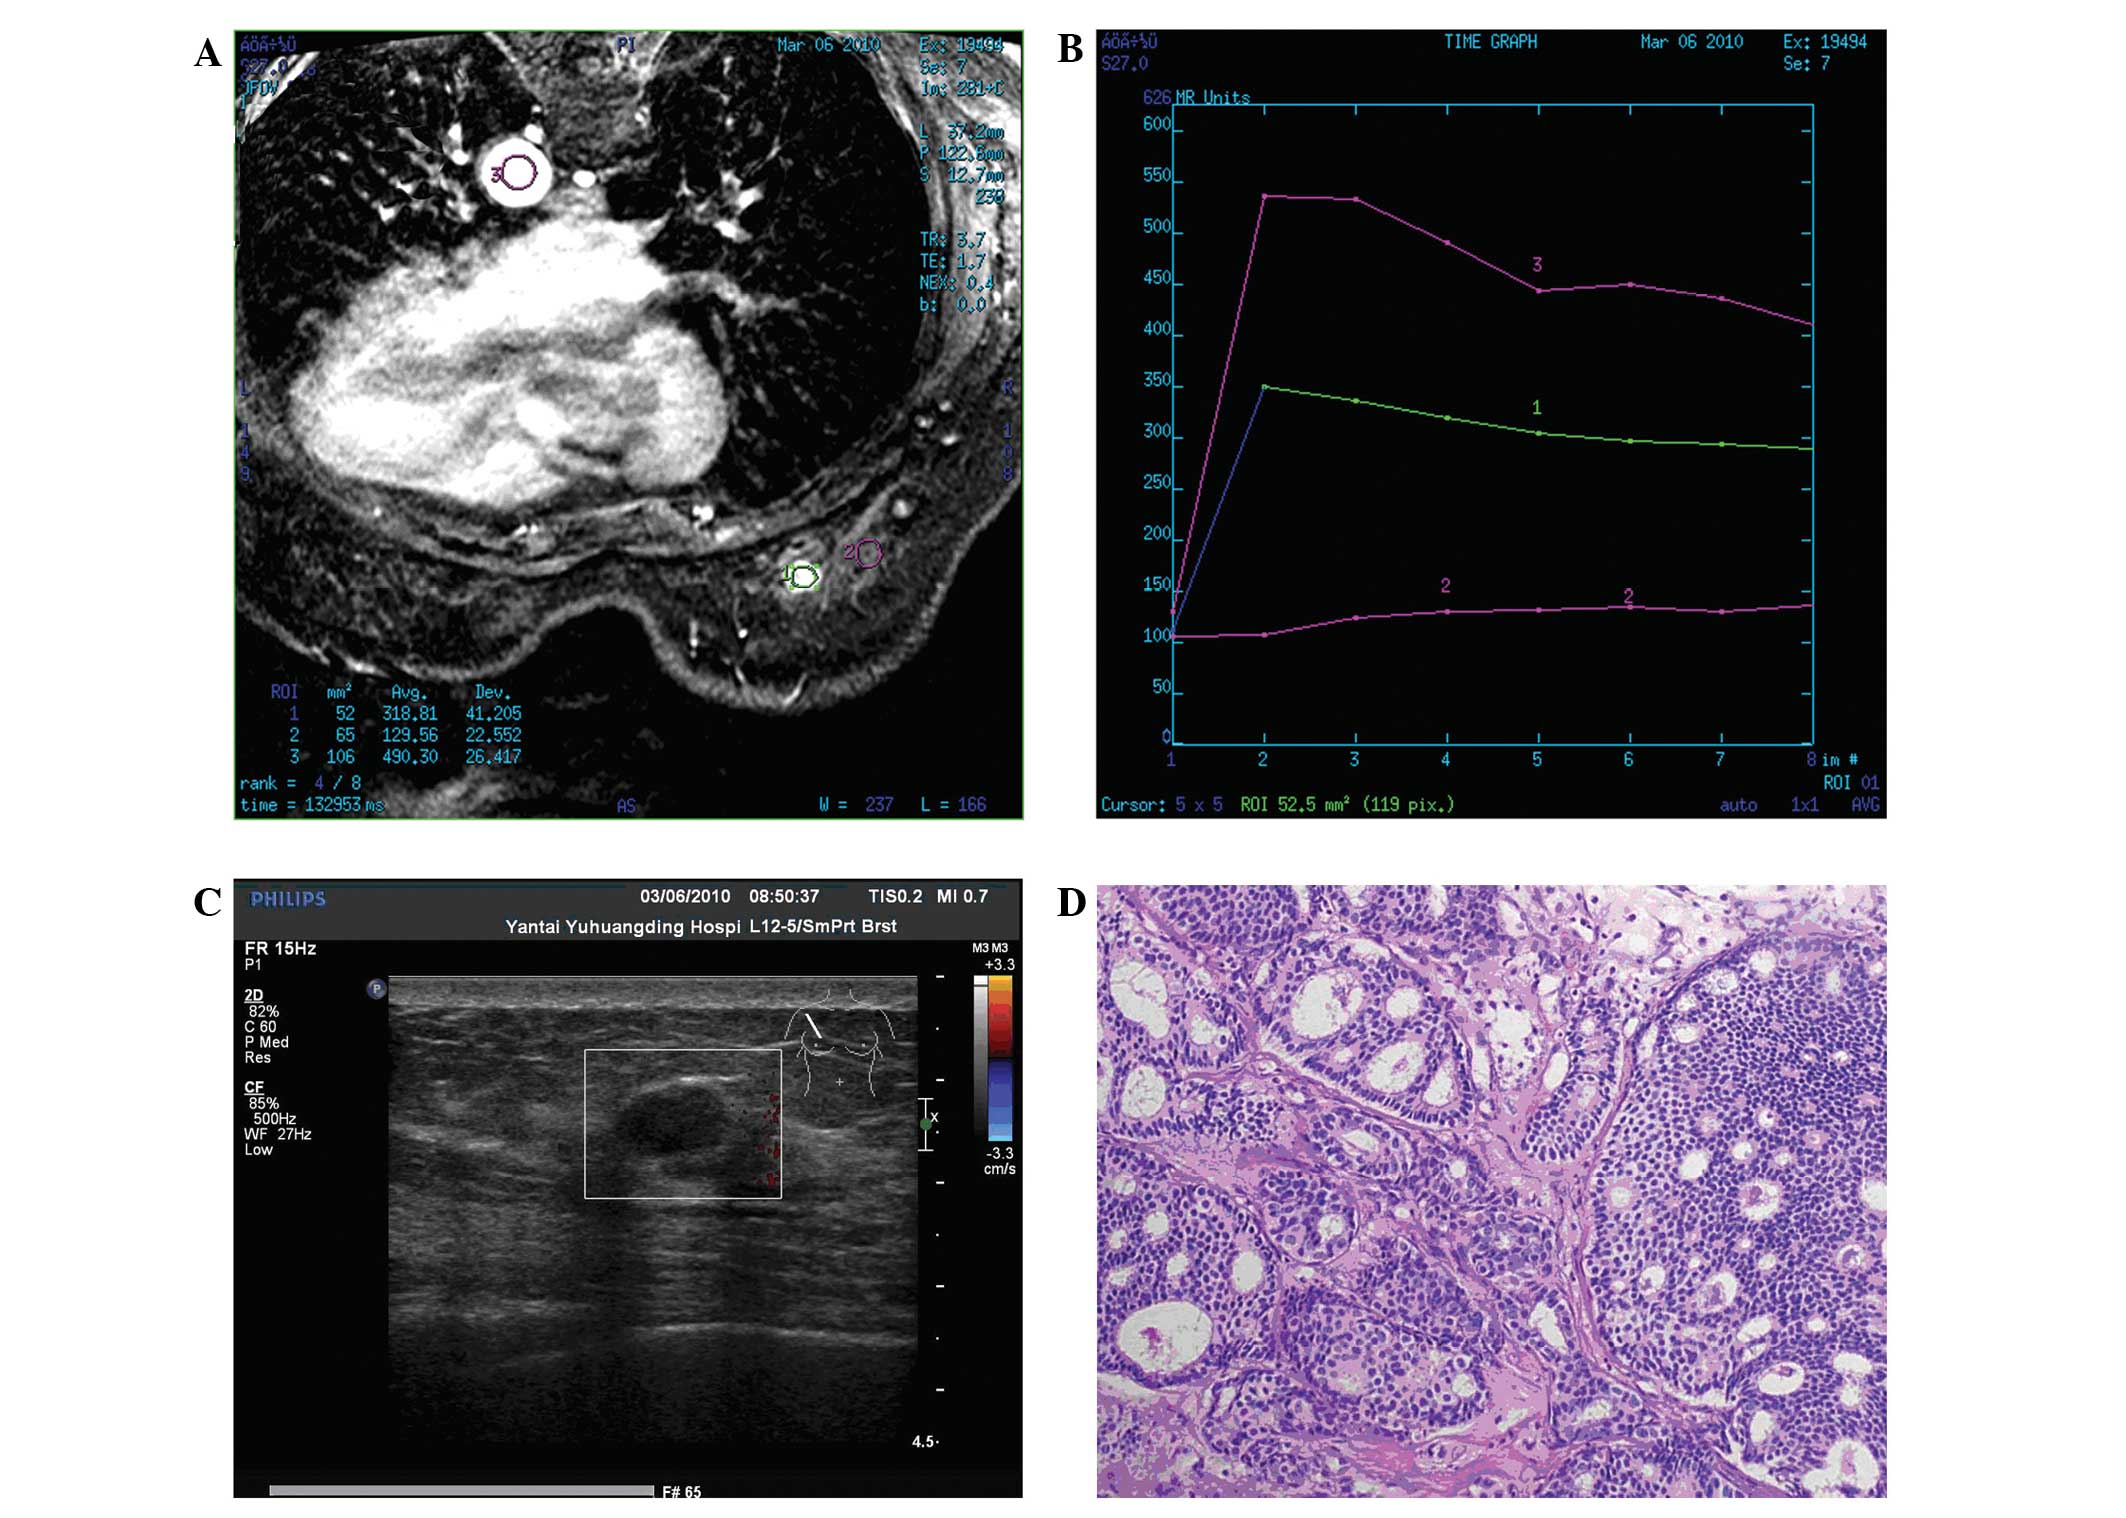

Nine cases of infiltrating cribriform carcinoma (ICC) of the breast are reported and the clinicopathological features, particularly the imaging findings, are analyzed in the present study. Sonograms revealed that all masses exhibited a hypoechoic internal echo texture (9/9) and that a number of masses presented with an irregular shape (8/9), obscure boundary (5/9), partially microlobulated (5/9) or well‑circumscribed (4/9) margins, and an inhomogeneous echo (8/9). Mammographic imaging revealed increased radiological density masses (6/8), and sand‑like calcification was not observed in all patients. In two patients, the tumors were mammographically occult. Magnetic resonance imaging performed on one patient revealed a slightly high signal intensity on fat‑saturated T1‑ and T2‑weighted images. Following contrast enhancement, a homogeneous early enhancement was revealed with a quick ascent and quick descent time‑density curve. Immunohistochemistry revealed that all ICCs expressed estrogen receptor and progesterone receptor, but that none were positive for human epidermal growth factor receptor 2. The Ki‑67 labeling index was 3.75% (range, 2‑5%) in the tumor tissue. Four patients were treated with mastectomy and the others with breast‑conserving surgery. Six clinically node‑negative patients underwent sentinel lymph node biopsy; three then received axillary lymph node dissection. Following surgery, three patients received adjuvant chemotherapy, radiotherapy and hormonal therapy, respectively. With a median follow‑up time of 38 months (range, 4‑70 months), one patient developed local recurrence following breast‑conserving surgery; axillary lymph nodes and distant metastases were not observed. This study confirms that this type of carcinoma has unique biological characteristics and a favorable prognosis, but that it remains possible to experience local recurrence.